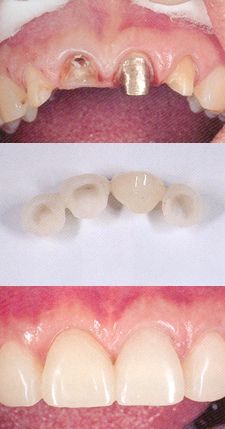

症例3.

オールセラミックというすべてセラミックで作られた被せ物です。